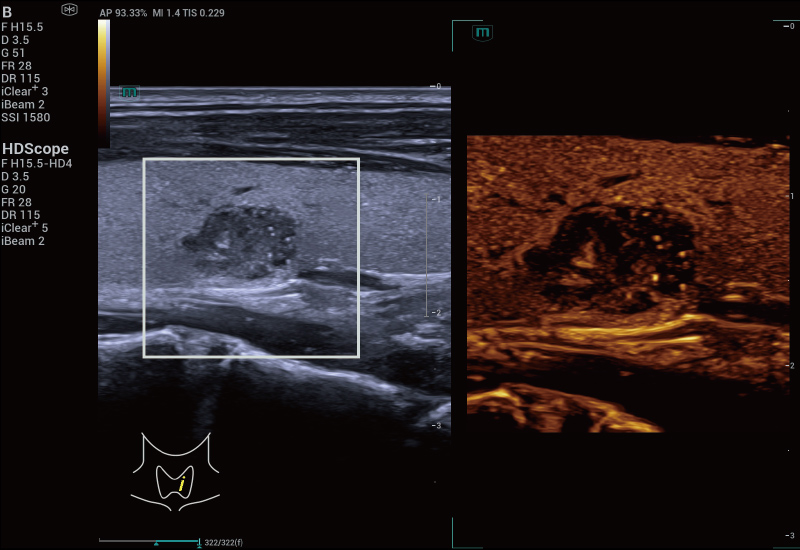

previously difficult to achieve. SR CEUS reveals the intricate

microcirculation details of lesions at the micron level, aiding in

microcirculatory perfusion studies in oncology.

Microvascular detection capabilities

Focal Nodular Hyperplasia | Density Map

Focal Nodular Hyperplasia | Direction Map

Focal Nodular Hyperplasia | Velocity Map